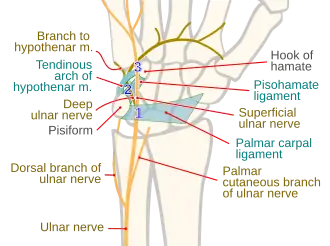

Hand

Ulnar nerve enters the palm of the hand via the Guyon's canal, superficial to the flexor retinaculum and lateral to the pisiform bone.[6]

Here it gives off the following branches:[7]

- Superficial branch of ulnar nerve - supplies the palmaris brevis and gives digital branches to the medial one and a half fingers.[6]

- Deep branch of ulnar nerve - It accompanies the deep branch of the ulnar artery. It passes backwards between the abductor digiti minimi, flexor digiti minimi, and opponens digiti minimi, supplying all the three muscles, and lying on the hook of hamate bone. It then turns laterally, supplying the 3rd and 4th lumbricals and all the palmar interossei muscles and dorsal interossei of the hand. It terminates by supplying the adductor pollicis.[6]

- Articular branches to the wrist.[6]